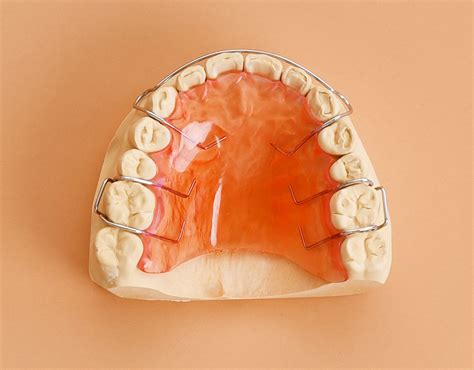

Después de quitar los brackets o los alineadores invisibles, los dientes todavía se están afianzando en las encías. Para evitar que los dientes vuelvan a su posición inicial, es crucial utilizar retenedores. Existen diferentes tipos de retenedores:

- Retenedores Fijos: Son alambres delgados adheridos a la cara interna de los dientes, proporcionando una retención constante.

- Retenedores Removibles: Pueden ser de plástico transparente (tipo Essix) o de acrílico con un alambre metálico (tipo Hawley). Es importante que se limpien de manera adecuada los retenedores removibles antes y después de cada uso. Asimismo, se deben utilizar todas las noches y seguir los consejos de tu dentista.

El ortodoncista indicará cuánto tiempo se deben usar los retenedores. En general, se recomienda llevarlos todas las noches de forma indefinida.